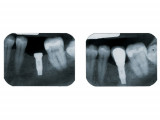

Implants

- Un implant dentaire est une racine artificielle placée par le chirurgien-dentiste dans l'os alvéolaire de l'un des maxillaires en remplacement de la racine d'une dent extraite et servant de support à une prothèse.

Sa forme est généralement cylindrique ou légèrement conique, ressemblant à une vis, en titane ou en zircone, avec une connexion au niveau supérieur, à l'emplacement de la gencive, pour permettre la pose d'un élément prothétique par vissage ou scellement.

Son diamètre varie entre 3 et 5mm et sa longueur entre 8 et 15mm.

Il faut attendre après la pose de l'implant, l'ostéo-intégration, qui peut durer plusieurs mois. L'implant va se souder complètement avec l'os et contrairement à la dent il n'y a pas de ligament alvéolo-dentaire.